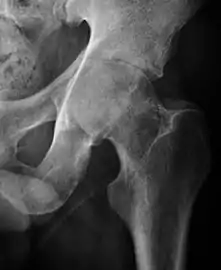

Plain radiography allows us to categorize the hip as normal or dysplastic or with impingement signs (pincer, cam, or a combination of both). Besides these, pathologic processes like osteoarthritis, inflammatory diseases, infection, or tumors can also be identified (Figure 1).[1]

Figure 1.

Osteoarthritis

In adults, one of the main indications for radiographs is the detection of osteoarthritic changes (Figure 1(e)). Nevertheless, radiographs usually detect advanced osteoarthritis that can be graded according to the Tönnis classifications. The grading system ranges from 0 to 3, where 0 shows no sign of osteoarthritis. Intermediate grade 1 shows mild sclerosis of the head and acetabulum, slight joint space narrowing, and marginal osteophyte lipping. Grade 2 presents with small cysts in the femoral head or acetabulum, moderate joint space narrowing, and moderate loss of sphericity of the femoral head. Grade 3 is the severest form of osteoarthritis, which manifests as severe narrowing of the joint space, large subchondral cyst with productive bone changes that may lead to deformity of the bone components of the joint, while secondary osteoarthritis due to calcium pyrophosphate deposition can be diagnosed when calcification of hyaline cartilage and fibrocartilage is detected.[1]

There are other pathological conditions that can affect the hip joint and radiographs help to make the appropriate diagnosis. Acute bacterial septic arthritis can be diagnosed by radiographs when a fast regional osteoporosis and destructive monoarticular process develops (Figure 1(f)). In case of tuberculous or brucella arthritis it is manifested as a slow progressive process, and diagnosis may be delayed.[1]